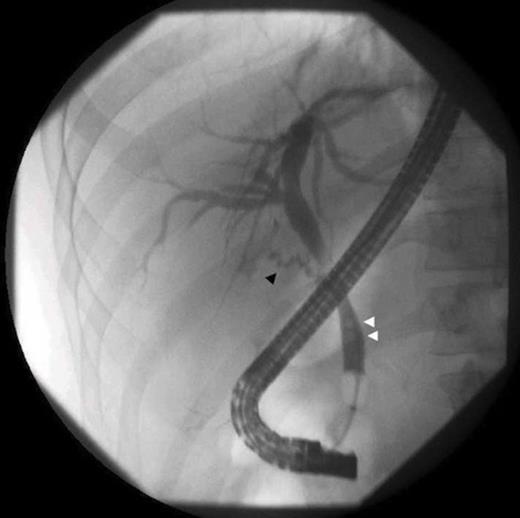

ERCP shows a residual cystic duct (black arrow), and choledocholithiasis (white arrows)

Over seven months, he had continued frequent recurrent attacks of acute cholecystitis, and choledocholithiasis. His symptoms included frequent nausea, vomiting, persistent sharp right upper quadrant pain, fever, and jaundice, which precipitated multiple Emergency Department visits to multiple institutions. The patient presented to our institution with an outside ultrasound that demonstrated multiple residual stones, a sonographic Murphy’s sign, and dilated common bile duct of 9 mm. Choledocholithiasis was confirmed by MRCP (Fig. 1) and gallstones were visualized in the remaining portion of the gallbladder by CT, (Fig. 2) although there was no evidence of gallbladder wall thickening or pericholecystic fluid. Preoperatively, an ERCP with sphincterotomy was performed to extract the remaining common bile duct stones (Fig. 3).